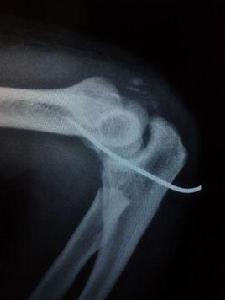

骨頭錯位● 及時檢查扭傷嚴重不妨對關節做x光照像檢查,因為嚴重扭傷與骨折經常不易區分。如確診,可在扭傷的肢體或手指部位鑄敷石膏模。